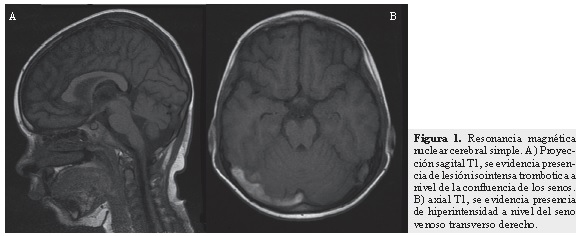

Se realizó Doppler arterial transcraneano y se encontraron, a nivel de arterias cerebrales medias, cambios compatibles con estado de hiperperfusión en las regiones izquierdas que pueden estar en relación con edema cerebral de ese lado. En la RNM cerebral simple y con gadolineo más angioresonancia se evidenció trombosis de senos venosos cerebrales profundos (parcial de seno longitudinal superior, completa de seno venoso transverso de predominio izquierdo, parcial a nivel de senos venosos sigmoideos y trombosis a nivel de la confluencia de los senos) (Figuras 1 y 3). Se evidenciaron accidentes cerebrovasculares (ACV) isquémicos venosos gangliobasales izquierdo y derecho, talámico izquierdo y hemisferios cerebelosos. Así mismo, se vio edema cortical en las regiones occipitales bilaterales y hemisférica izquierda por proceso de congestión venosa veno-capilar y se observaron áreas de necrosis laminar cortical fronto-parietales izquierdas. En la RMN cerebral de control hay evidencia de ACV isquémico en los globus pallidus bilaterales de mayor compromiso en región gangliobasal izquierda (Figura 2) y ACV isquémico en el mesencéfalo a nivel de los pedúnculos cerebrales de forma bilateral, sin evidencia de progresión de la trombosis con respecto a la RNM previa.